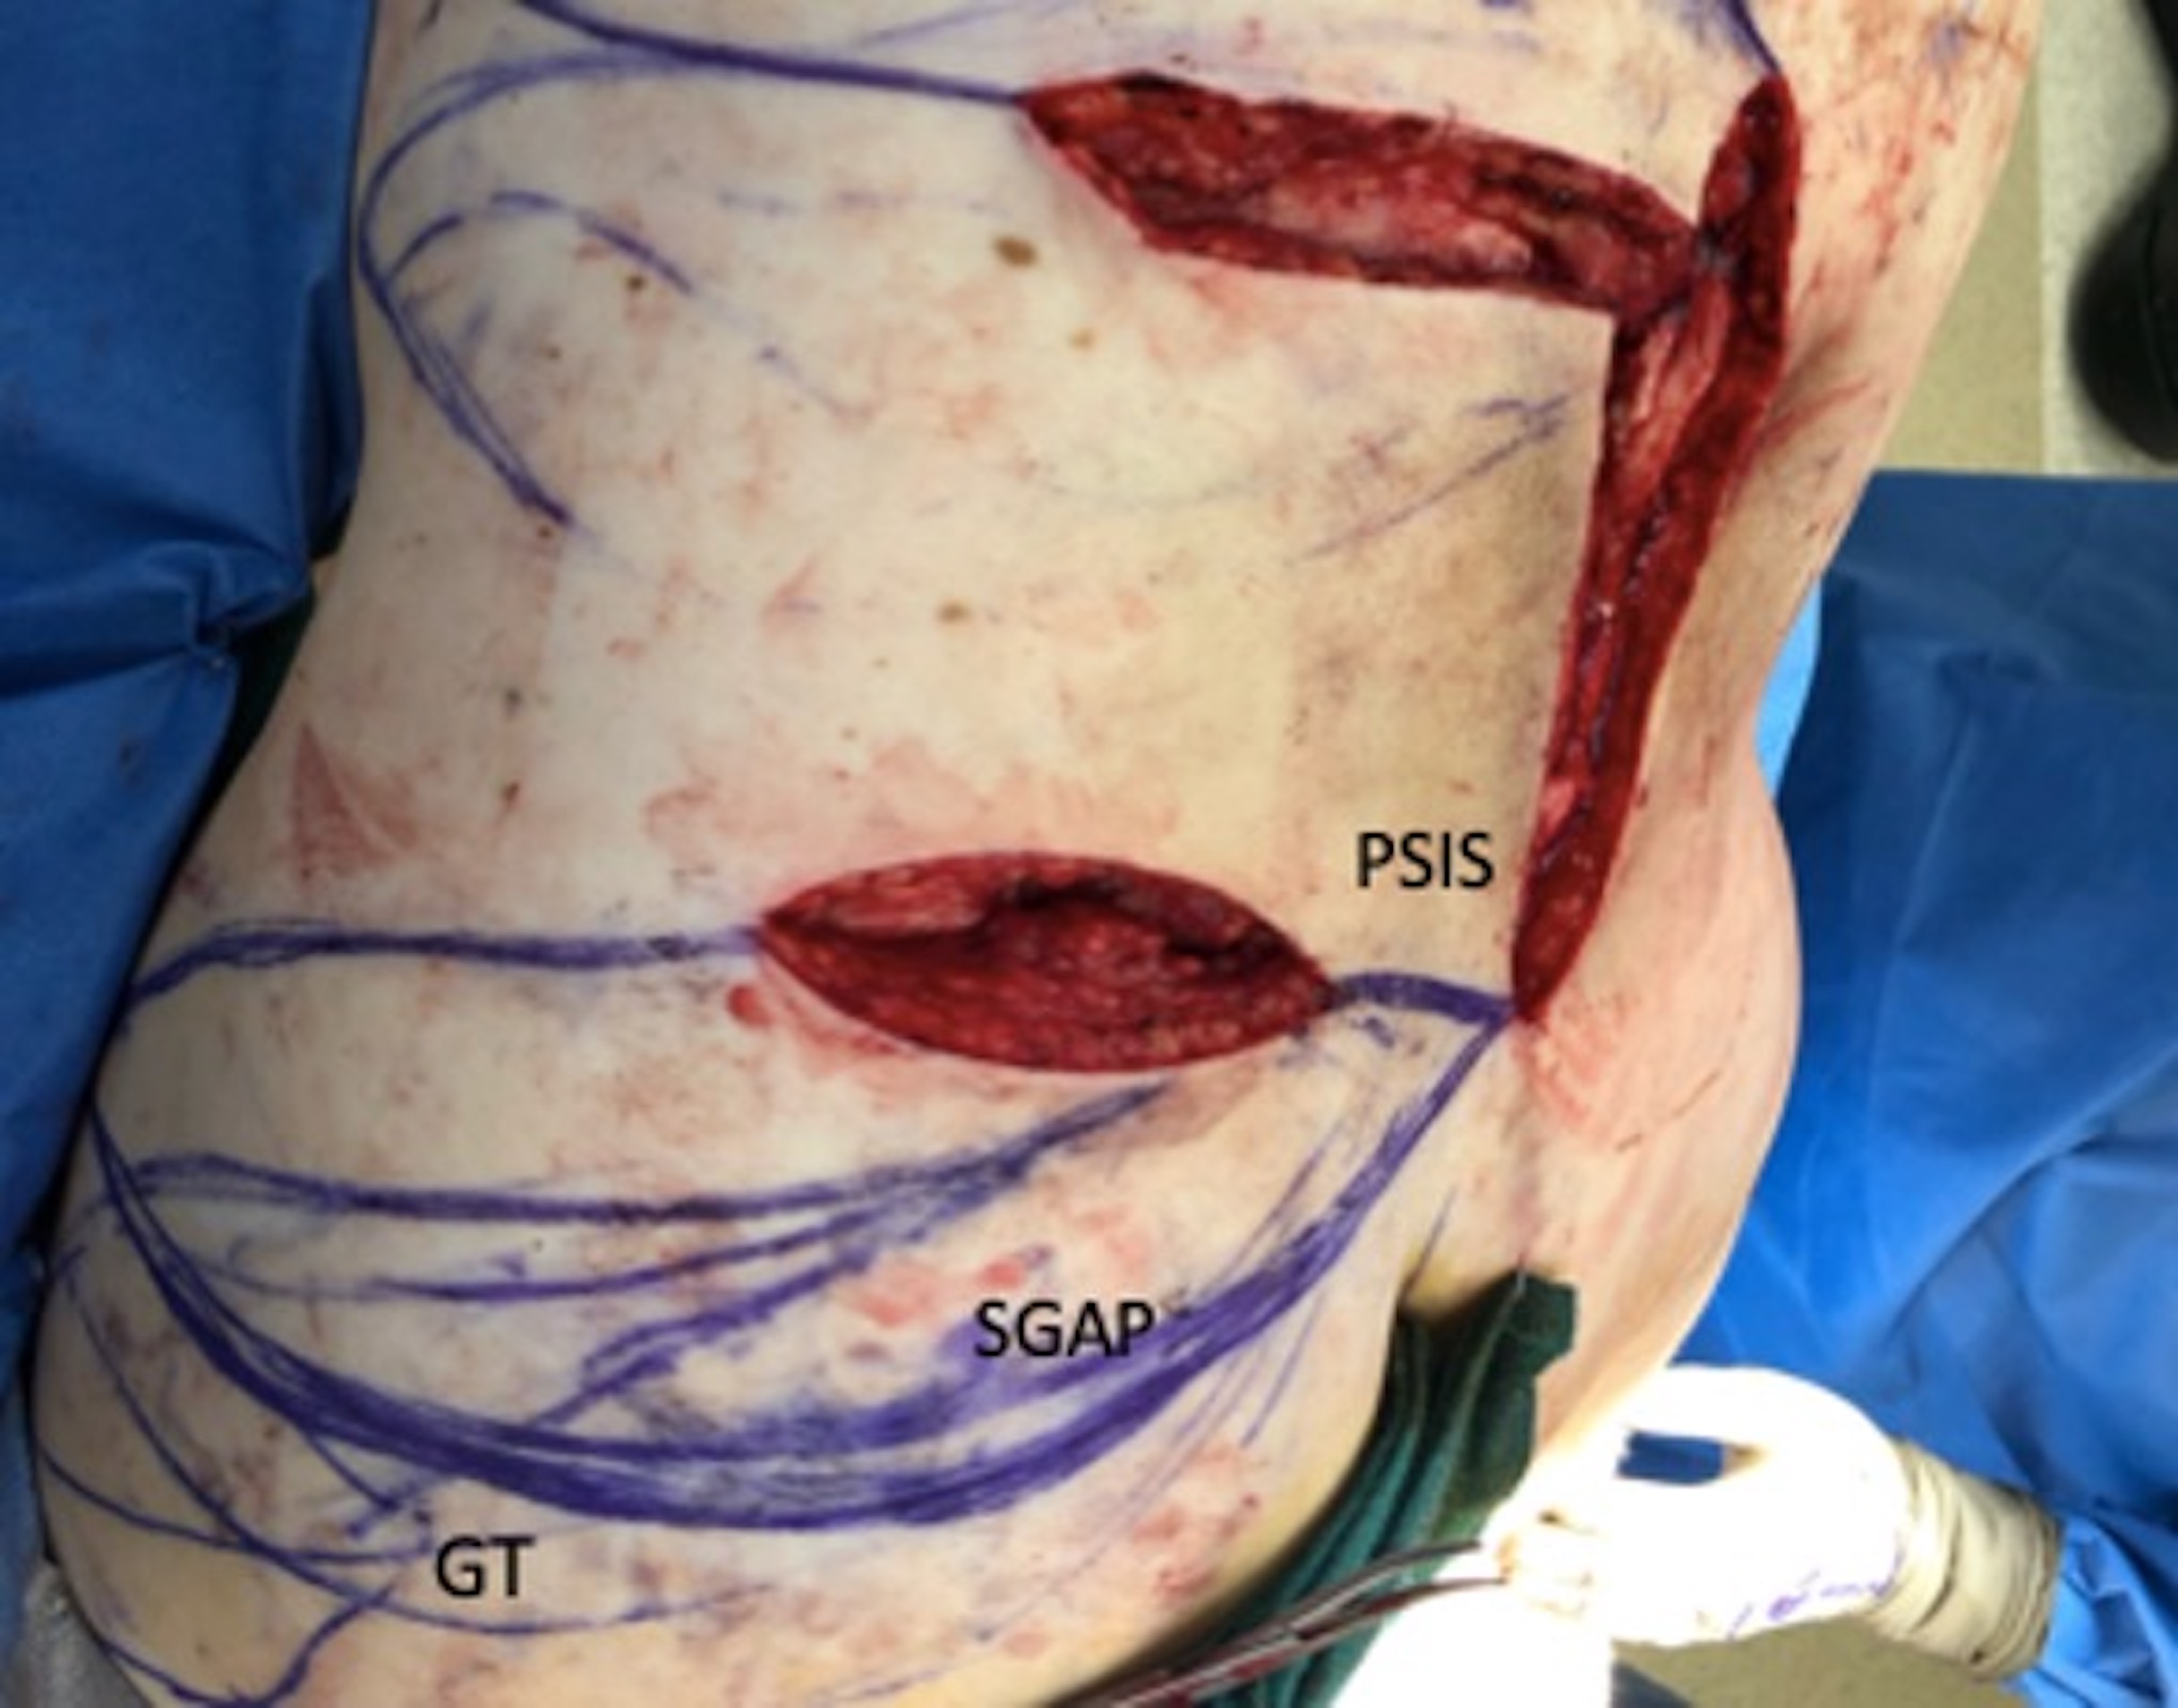

For lumbosacral defects specifically, the contralateral zone 1 or ipsilateral zone 1 and 2 perforators arising from the posterior intercostal, lumbar, or superior gluteal artery systems are all options on which to base a flap. Defect size, donor tissue quality and laxity, as well as perforator caliber determine which perforator is most appropriate in a given patient. In this case, to take advantage of the laxity in the “love-handle” area, a superior gluteal artery perforator flap was initially planned; however, no sizable cutaneous perforator could be identified via an initial exploratory incision incorporated into a preliminary flap design (Figure 5). Subsequently superior to the defect, where there was considerable laxity in the upper flank, a dorsal intercostal artery perforator was randomly identified with doppler ultrasound and interrogated intraoperatively, confirming it to be usable based on its size (~1.5 mm) and pulsatility. The flap was islanded and raised in a subfascial plane, and the perforator dissected through the deep fascia to avoid constriction as it made a gentle 90-degree turn (Figure 6). Robust flap perfusion was confirmed with indocyanine green angiography (Figure 7). However, following flap inset and direct closure of the donor site, the flap was noted to be somewhat congested. Thus, one of the edges of the flap was left open with a negative pressure dressing. After a week, the inset was completed, leading to a well-healed flap that resurfaced the wound (Figure 8).